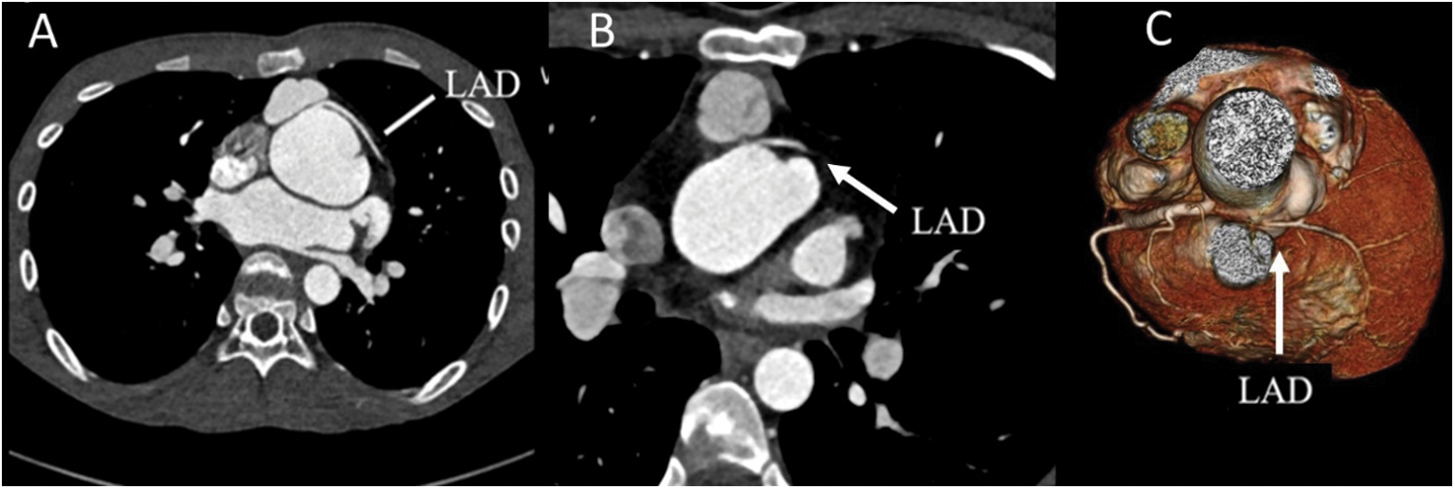

Among subjects with a single coronary artery and common ostium of the RCA and LAD 60% (6 out of 10 patients) reported multiple episodes of chest pain (all symptomatic patients also had prepulmonic course of coronary artery after ASO), compared with 9% (3 of 33 cases) of patients with other coronary artery patterns (adjusted OR = 14.3%, 95% CI (2.5–82.3); P = 0.003) (Table 4). Of those who have preoperative unusual coronary patterns, prepulmonic course was found in 11 (55%) patients including 1R-2LCx, 1RL-2Cx, 1RLCx, and 2LCxR (Figs. 2 and 3). Six of 11 (54%) patients in this group experienced significant chest pain (crude OR = 11.6%, 95% CI (2.1–62.2), P = 0.001). Interarterial courses were seen in nine patients (20%), and two of those patients reported significant chest pain (22%). Among them, seven patients had an interarterial course of LAD or LMCA, while two patients had an interarterial course of RCA (Fig. 4). Acute take-off angle occurred in three patients (6.9%); each had high take-off (coronary ostia located above the sinotubular junction) [29], but none had significant coronary stenosis (Fig. 5). The mean aortic root z score in patients post-ASO was 4.71 ± 2.4 [30].

Figure 3: Coronary CTA with 3-dimensional reconstruction. (A) shows the origin of LAD from the right coronary cusp with prepulmonic course in patients with 2LCxR. (B–D) show the prepulmonic course of RCA in 1RL-2Cx, 1RLCx and 1R-2LCx, respectively